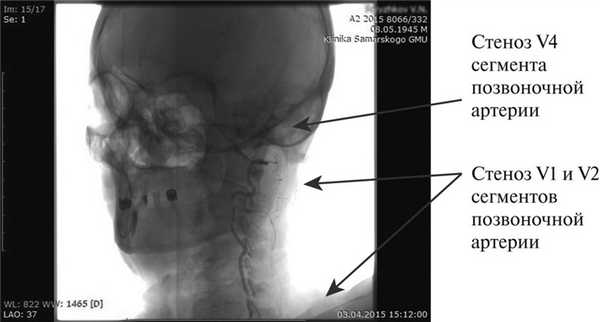

Больной С., 69 лет. Поступил в отделение хирургической ангионеврологии Клиники факультетской хирургии Самарского государственного университета 01.04.15. При поступлении предъявлял жалобы на головную боль, головокружение, слабость и онемение в левых конечностях, постоянный шум в ушах, неустойчивость при ходьбе. Стал отмечать медленное нарастание данных жалоб в течение последних 2 лет. Лечился консервативно у невролога поликлиники - без эффекта. При скрининговом УЗИ выявлены стенозы брахицефальных артерий (БЦА). Направлен в стационар. В неврологическом статусе при поступлении - феномен Гуревича-Манна, хоботковый симптом, легкая слабость иннервации VII пары черепно-мозговых нервов (ЧМН) слева, легкая слабость иннервации XII пары ЧМН слева. В позе Ромберга слабо устойчив, отклоняется влево, ходьба с закрытыми глазами - уклоняется влево до падения. Пальценосовые пробы выполняет с интенцией и промахиванием левой рукой. Отмечается мелкоразмашистый горизонтальный нистагм. Сила в конечностях 5 баллов. Пациенту выполнено дообследование: по данным УЗИ БЦА выявлены незначимые стенозы бифуркаций СА: справа - 30%, слева - 50% (бляшки неосложненные). Субтотальный стеноз V1 и V2 сегментов ПА слева, коллатеральный тип кровотока. При компьютерной томографии (КТ) выявлено диффузное поражение подкорковых ганглиев. При КТ-ангиографии - субтотальный стеноз V1 и V2 сегментов ПА слева, стеноз 80% в V4 сегменте ПА слева. На рентгеноконтрастной ангиографии стенозы сонных артерий: справа - 30%, слева - 50%. Субтотальный стеноз V1 и V2 сегментов ПА слева, стеноз 90% в V4 сегменте левой ПА (рис. 2).

Рис. 2. Больной С. Ангиография позвоночной артерии слева до операции.